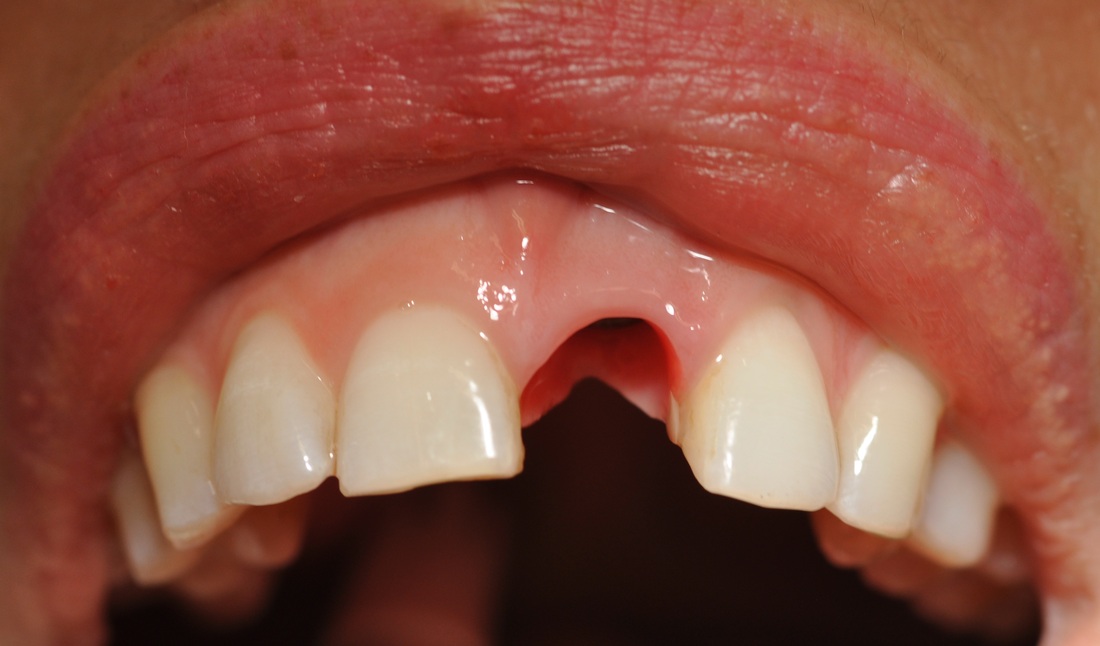

ANTERIOR IMPLANT

A graduate student came to our DENTOLOGY practice with a broken upper front tooth. Dr. Andrews recommended to replace it with a dental implant. Due to high smile line and anatomy of the area, this type of cases is considered to be one of the most challenging for a dentist to treat.

Without any incisions, Dr. Andrews removed the broken root and placed an implant along with a bone graft during the same surgery. Immediately, a temporary crown was attached to two other front upper teeth to form the ideal shape for the soft tissue profile. A few months later, 3D Intraoral scan was taken and Dr. Andrews used Virtual Prosthodontics (CAD) and Reverse Restorative Rehabilitation Protocol to design Full Contour Zirconia (FCZ) screw-retained Implant Crown.

Then the crown was milled (CAM) and sintered by a specialized Milling Center. Once it had been received, the FCZ restoration had been custom shaded and glazed at DENTOLOGY in-house lab. During the patient’s next and final visit, all-ceramic crown was delivered via screw-retained fashion to prevent any complications associated with cement retention under the gum margin (the most common reason for implant failures in intraorally cemented cases).